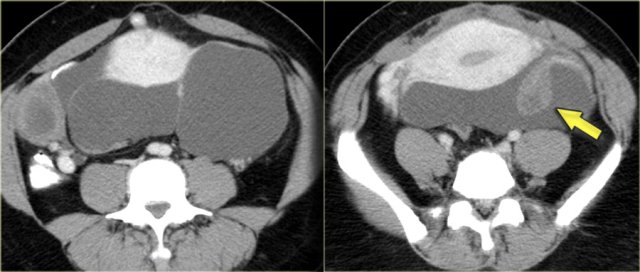

When these peritoneal inclusion cysts become very large, they may extend into the upper abdomen as is seen in the case on the left.

Notice that the left ovary is encircled by the cyst (arrow).

There are also some enhancing septa.